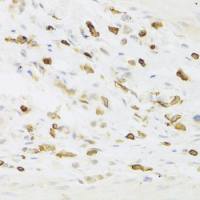

FACS analysis of human peripheral blood granulocytes using GTX74695 CD66a + CD66c + CD66d antibody [YTH71.3].